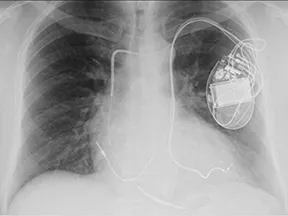

Small ICD Programming Change May Extend Lives, Reduce Needless Shocks

Study: Cardiac Resynchronization Therapy Best to Treat Heart Block